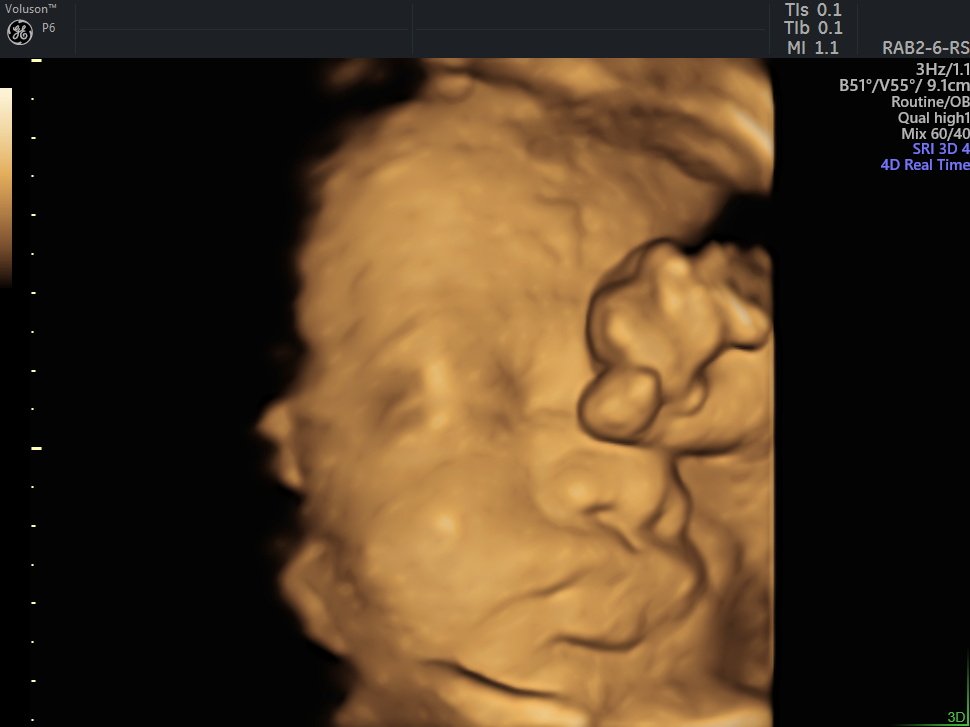

4 D Ultrasonografi

4 Boyutlu (Renkli) Ultrason ve Doppler Ultrasonografi